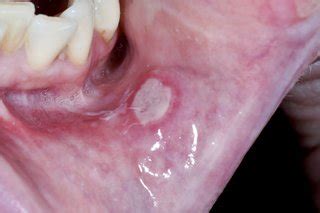

Recurrent stomatitis, also known as recurrent aphthous ulcers, is a common condition where painful mouth ulcers keep coming back at intervals. Though not dangerous, they cause significant discomfort while eating, speaking, and swallowing.

• Painful round or oval ulcers

• Burning or tingling sensation before ulcer appears

• Difficulty in eating and speaking

• Recurrent episodes